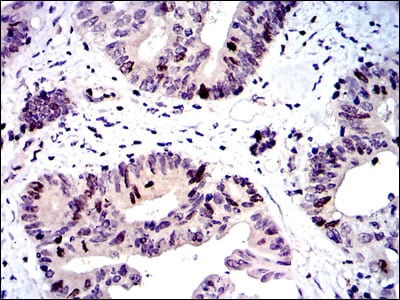

Immunohistochemical analysis of paraffin-embedded human cervical cancer tissues using BIRC5 mouse mAb with DAB staining.

Immunohistochemical analysis of paraffin-embedded human colon cancer tissues using BIRC5 mouse mAb with DAB staining.